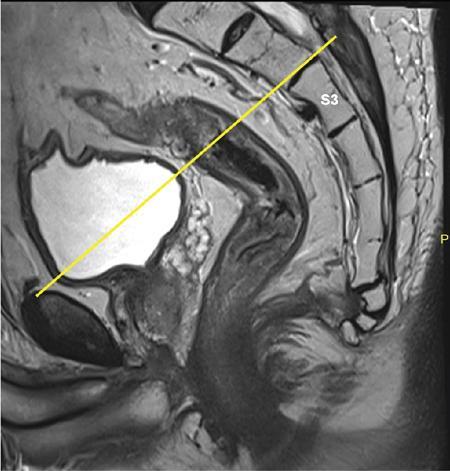

Sumit Mukhopadhyay, Saugata Sen, Aditi Chandra, Argha Chatterjee, Priya Ghosh, Anisha Gehani Cloaca is the part of hindgut caudal to the attachment of the allantoic diverticulum. It divides into a broad anterior urogenital (vesicourethral and urogenital sinus) part and a narrow posterior anorectal compartment/primitive rectum, separated by the urorectal septum. This anorectal compartment gives rise to mid rectum and lower rectum and upper part of anal canal proximal to dentate line. The peritonealized upper part of rectum develops from hindgut proximal to cloaca. The distal most part of anal canal below the dentate line develops from invaginated ectoderm known as proctodeum (Fig. 8.5.1). Initially during development, the rectum is suspended from the posterior abdominal wall by a mesentery, along with the rest of the gut. After completion of rotation of the gut, rectal mesentery fuses with the posterior abdominal wall, majority of rectum becomes retroperitoneal and hindgut mesentery is seen as mesorectum. The artery of the hindgut is inferior mesenteric artery. Anatomically, classically taken as 6 inches (approximately 15 cm), or beginning at the level of S3 vertebra. Surgically defined as 15–18 cm from anal verge (AV), thus anal canal and rectum are considered together for the purpose of surgical and radiological anatomy, though management differs in cases of rectal adenocarcinoma and anal squamous cell carcinoma (SCC). Various trials on rectal cancer neoadjuvant therapy have taken different lengths of cut-off for rectal cancer starting from AV: 9 cm, 12 cm, 15 cm or 16 cm (Table 8.5.1). Rectum continues as sigmoid colon superiorly. The point of transition between rectum and sigmoid colon is controversial. Anatomically, this is the point where sigmoid mesocolon ends, appendices epiploicae are lost and taenia coli gradually converge and disappear. There is no single transition point between these features. These features are not visible to the radiologist/endoscopist as well. Several features defining rectosigmoid junction/transition are variously accepted by different radiologists: Rectum continues as anal canal, which opens to the exterior at AV (mucocutaneous junction). Anorectal junction (ARJ) is considered to be the point at which the angle of the long axis changes, and corresponds to the upper border of puborectalis muscle. The change in axis of anal canal and rectum is well visualized on sagittal MRI. Dentate line lies along the anal crypts (the openings of anal glands), and vertical folds called columns of Morgagni extend superiorly from the dentate line. Anatomists consider the dentate line to be the landmark for ARJ, but the dentate line lies distal to the puborectal sling, and this definition is not clinically relevant. Anal canal is directed posteroinferiorly. At ARJ, the long axis of rectum changes so that it is directed anteroinferiorly. Mid rectum and upper rectum follow the sacral concavity, and the long axis of rectum is again directed posteroinferiorly. Upper rectum is frequently mobile and may not be in midline. Three incomplete folds consisting of mucosa, submucosa and circular muscles, named as Valves of Houston, are seen within the lumen of rectum during endoscopy, but these are not visualized radiologically. The middle valve is roughly at the level of anterior peritoneal reflection, and the superior most valve is at the level of rectosigmoid junction. Surgically and radiologically, rectum is divided into thirds: lower third, middle third and upper third (Table 8.5.2). Most commonly, this division is according to distance or length from AV. Lower third is 0–5 cm, middle third is 5–10 cm, upper third is 10–15 cm from AV (Fig. 8.5.6). Some radiologists define low rectum as 6 cm or less from AV, mid rectum as 7–11 cm and upper rectum as 12–15 cm. The justification of defining low rectum as 6 cm or less from the AV is that, management of most of the tumours at this location suffers from surgical challenges due to tapering of mesorectum and proximity of other pelvic structures. These tumours have a higher rate of CRM positivity, abdomino-perineal resection (APR) and permanent stoma, higher rates of recurrence and mortality, poor function of stoma after sphincter preservation. Another way of defining low rectum, surgical management of which differs from the upper two-thirds, is the portion lying distal to the proximal origin of levators at pelvic side wall. This definition was provided by the English National Low Rectal Cancer Development Programme (LOREC) and is best visualized in the coronal plane by a line joining proximal origins of levators at pelvic side walls (Fig. 8.5.7). ARJ is an important landmark in the management of rectal cancer. Distance between lower border of the tumour and ARJ is important for treatment planning. ARJ is defined as the point at which puborectalis fuses with the levator muscles, and the long axis of rectum changes from anteroinferior to posteroinferior at this point. Its upper extent begins few centimetres above the dentate line, and its length varies from 2–5 cm from AV. Histologically the proximal end of the anal canal is the point at which the columnar epithelium of the rectum becomes the transitional epithelium. Anal canal mucosa has several longitudinal columns, known as anal columns, which end at the dentate line. Below the dentate line the mucosa is smooth and transitions into skin at AV. Approximately at the level of dentate line, the internal anal sphincter (IAS) ends, and the smooth mucosa leads to the intersphincteric plane, distal to which the external anal sphincter extends up to the AV (Fig. 8.5.8). Upper third of rectum is anteriorly covered by peritoneum. Peritoneal covering gradually widens superiorly till it is covered by peritoneum on all sides at the level of sigmoid colon. The exact level of peritoneal reflection varies between individuals, and is quite often seen in axial and sagittal MRI. In axial T2-weighted MRI, a thin hypointense layer with V-shaped attachment to anterior rectal wall is seen representing the anterior peritoneal reflection. This is known as the ‘sea-gull’ sign. Mesorectum and mesorectal fascia (Fig. 8.5.10): lower two-thirds are surrounded by extraperitoneal fat and connective tissue known as mesorectum, which contains lymph nodes, nerves and blood vessels (descending branches of superior rectal artery and corresponding veins). Mesorectal fat is contained within a thin layer of fascia, known as mesorectal fascia (MRF). MRF separates mesorectal fat from extra mesorectal tissues of the pelvis. A relatively avascular plane of areolar tissue lies between MRF and parietal pelvic fascia, facilitating surgery. Importance: Assessment of structures within mesorectum is important for staging and prognostication of rectal cancer. Mesorectal node involvement is N disease. Tumour extension within mesorectal vessels is known as extramural vascular invasion (EMVI) and is thought to be associated with higher chances of vascular dissemination and distant metastases. MRF forms the boundary of the surgical excision plane in total mesorectal excision (TME) – the standard surgery for rectal cancers at present. It is important to understand the various fascial reflections of the pelvis in order to understand pathways of disease spread. The plane between the MRF and the pelvic fascias is the surgical plane. Posteriorly, covering the sacrum, presacral venous plexus and hypogastric nerves, lies the presacral fascia. It fuses with MRF inferiorly at the level of levator ani muscle. The space between presacral fascia and MRF is known as the retrorectal/rectosacral/pelvirectal space, and that between the sacrum and presacral fascia is the presacral space. The presacral fascia continues laterally as the parietal pelvic fascia which covers the lateral pelvic wall. It has two lamellae which encase the pelvic visceral nerves as they course forward from the sacrum to the anterior pelvic organs. The rectosacral fascia/Waldeyer fascia, called as rectosacral ligament by anatomists, is a thickening arising from presacral fascia and running forward to meet the MRF. This divides the rectosacral space into a superior and an inferior compartment, communicating with each other. In males, anteriorly, between the rectum and prostate-seminal vesicles, lies the rectoprostatic fascia/Denonvillier fascia. It is difficult to distinguish from the closely related MRF, and carries the hypogastric nerve and vascular branches to the prostate and male genital organs. In females, anterior to the MRF, lies the rectovaginal septum. According to most views, this septum consists of two layers. The anterior layer corresponds to Denonvillier fascia, and extends from the pelvic floor to the posterior wall of vagina and uterus. The posterior layer is in close relation to the MRF, runs from the pelvic diaphragm and ascends to the peritoneal reflection before fusing with the rectal wall. The lateral rectal ligaments are controversial structures as they are not visualized by imaging and may not carry important structures such as nerves and vessels. However, in some cases, the middle rectal artery may run through them and the accompanying lymphatics may provide a pathway between mesorectal and extra mesorectal lymph nodes. In females, the pelvic floor may be considered to have three compartments, anterior compartment containing bladder and urethra, middle compartment containing the vagina and the posterior compartment containing the rectum. These compartments are supported by the endopelvic fascia and levator ani muscle. The levator ani has several compartments, of which the two most important ones are the iliococcygeus and puborectalis. The iliococcygeus starts as the same fibres as the EAS, and then fans out as a sheet to insert at the pelvic sidewall at the tendinous arch. Posteriorly these fibres fuse in the midline to form the levator plate/raphe. The pubococcygeus and puborectalis are considered together as pubovisceralis muscle. It inserts lateral to the symphysis pubis anteriorly, and forms a sling around the rectum, pulling it anteriorly. Components of the levator ani can be identified in T2-weighted MR images. In males, there are two compartments, anterior containing bladder, urethra, prostate and seminal vesicles and the posterior compartment containing the rectum. Pubococcygeus consists of pubourethralis and puborectalis in males. In sagittal images, the pubococcygeal line is an important reference line, drawn from the inferior border of symphysis pubis to the last joint of the coccyx, representing the level of pelvic floor. The H line is drawn from the inferior aspect of the symphysis pubis to the posterior wall of the rectum at the level of ARJ. This represents the anteroposterior width of the levator hiatus, and upper limit of normal is 5 cm. The M line is the vertical descent of the levator hiatus, drawn as a perpendicular line dropped from the pubococcygeal line to the posteriormost aspect of the H line, and should measure maximum 2 cm. The angle of the levator plate and the pubococcygeal line is also measured. In axial images, the entire normal levator is of uniform thickness and homogeneous low signal intensity. Coronal images show intact iliococcygeus muscle which is convex upwards. The upper half of the anal canal proximal to the pectinate line, the IAS, the conjoint longitudinal coat and the rectum drain lymph upwards into the mesorectal nodes (Fig. 8.5.11) and then lymphatics follow the superior rectal artery into the inferior mesenteric group of lymph nodes. The lymph from these nodes is carried by the intestinal lymph trunk(s). Anal canal below the dentate line along with the EAS drains to the superficial inguinal nodes. Lymphatic vessels also travel with the median sacral artery and drain the puborectalis muscle before finally joining the internal iliac lymph nodes. The internal iliac lymph nodes drain into pre-aortic and paraaortic (lumbar) lymph nodes and efferents from the nodes form the lumbar trunks. The intestinal trunks and the lumbar trunks enter the abdominal confluence of the lymph trunks at the level of the L1–L2 vertebrae, called the cisterna chyli, and then ascend as the thoracic duct. The pelvic lymph nodes lying outside the mesorectum are termed as ‘extra mesorectal lymph nodes’. Above the dentate line: blood supply is from the superior rectal artery, which originates from the inferior mesenteric artery, a branch of abdominal aorta. Superior rectal artery passes in the sigmoid mesocolon and divides into two branches behind the rectum at the level of S3 sacral segment. The superior rectal artery ends in the anal columns by forming a rich vascular plexus/anastomosis with the branches of inferior rectal artery. Blood returns via the superior rectal veins into the inferior mesenteric vein, which drains into the splenic vein and eventually into the portal venous system. Below the dentate line, the inferior anal canal obtains its blood supply from the inferior rectal artery, which is a branch of internal pudendal artery, originating from the anterior division of internal iliac artery. Blood returns via the inferior rectal vein, which drains into internal pudendal veins, internal iliac veins and ultimately into the inferior vena cava (systemic circulation). Thus anal canal is a site of portosystemic anastomosis. Due to the venous anastomoses that occur in the anal canal and the backup of blood flow into the rectal veins, haemorrhoids may be present in patients with portal hypertension. A small part of muscular wall of rectum and anal canal is also supplied by median sacral artery, a direct branch of abdominal aorta arising at the bifurcation of aorta. Nerve supply: The inferior hypogastric plexus lies laterally on the surface of MRF on both sides. It receives sympathetic nerve fibres from the superior hypogastric nerves and parasympathetic ‘nervi erigentes’ from the laterally situated sacral nerves (S2–S4). Laterally, inferior rectal branches of the pudendal nerves and internal pudendal arteries cross the ischio-anal fossa to supply the external sphincter and anal mucosa. T2-weighted small FOV images reveal the layers of rectal wall and details of perirectal soft tissue and pelvic floor most accurately. For adequate assessment of the integrity and involvement of different layers, axial images are needed, which should be obtained perpendicular to the axis of the rectum in that segment. Angle of acquisition should be altered according to the change in axis of rectum (Fig. 8.5.12). The layers of rectal wall from inside to outside are (Fig. 8.5.10): When examining the anorectum with a radial scanning echoendoscope, the internal and EASs can be seen as two distinct rings. The inner hypoechoic ring of tissue represents the IAS the outer hyperechoic tissue ring represents the EAS. The thickness of normal IAS is 2–3 mm, and for EAS: 7–9 mm. The IAS becomes thicker and more hyperechoic with age, while the EAS tends to become thinner with age. Endoscopically, rectum begins at the dentate line and extends to 15–20 cm from the AV. The normal five-layer appearance of rectal wall in EUS is as follows: Imaging in the rectum and anal canal region is mainly for staging of tumours. The most common neoplasm of this region is rectal cancer and preoperative imaging evaluation is required not only for staging early and advanced disease but also for assessing response to treatment and for surgical planning. The techniques described here will mainly pertain to rectal and anal neoplasms. Plain radiographs have a limited role in the evaluation of rectal neoplasms. Primarily, it may be used as a modality in the emergency setting when patients come with constricting colorectal strictures causing large bowel obstruction. Radiographs of the abdomen in supine and erect positions are performed to look for features of bowel obstruction, air-fluid levels and free air under the domes of diaphragm in case of perforation, respectively. Conventional luminal contrast study is now obsolete for diagnosis of tumours in the rectum and anal canal and have been replaced by cross-sectional imaging. Sinogram studies with diluted iodinated contrast have been performed to detect extent of rectal fistulae. Endorectal Ultrasound (ERUS) can differentiate between the layers of the rectal wall and helps detect and stage tumours within the different layers of the rectum. ERUS can view the rectal mucosa in 360 degrees. The layers visualized include rectal mucosa, muscularis mucosa, submucosa, muscularis propria and area between the muscularis propria and perirectal fat. The role of ERUS in rectum is primarily in staging and in posttreatment surveillance of rectal adenocarcinoma. Staging of early tumours requires an ERUS due to its superior diagnostic performance for differentiating T1 from T2 tumours in comparison to other cross-sectional imaging modalities like MRI. As far as surveillance is concerned, endoscopy is mandated as it can detect early asymptomatic recurrences which improves overall survival (OS). This is substantiated by multiple recent meta-analyses in literature. Hence, even for patients on ‘watchful waiting’ as a treatment option after chemoradiotherapy, it is imperative to perform a DRE, EUS, CEA and correlate the findings with restaging MRI. The various recommendations for postoperative surveillance for rectal cancer using endoscopy are enumerated in Table 8.5.3. ASCO: American society of clinical oncology; ESMO: European society for medical oncology; NCCN: National comprehensive cancer network; USMSTF: United States Multi-Society Task Force. Drawbacks include heterogeneity in operator skill and operator dependency as well as inability to pass stenosing lesions. Poor depth of penetration of the probe results in reduced visualization of the mesorectal fat, limited assessment of pelvic side walls and EMVI and reduced diagnostic accuracy for asserting involvement of CRM. Multidetector CT (MDCT) is the primary imaging modality used for rapid evaluation of not only bowel pathologies (luminal or mural) but also for evaluation of surrounding structures such as vessels, lymph nodes and mesentery. The ability to obtain high-quality clinical images through multiplanar reconstructions make it one of the most robust examinations for the initial evaluation of most bowel related pathologies. A routine abdominal CT scan would include acquiring a noncontrast axial image, followed by a portal phase image (at 70–90 seconds). However, for more detailed evaluation of solid organs, a general imaging dataset would include an unenhanced CT, followed by arterial phase (20–30 seconds), portal venous phase (70–90 seconds) and a delayed phase at 3 minutes. Many centres around the world omit the noncontrast scan to reduce radiation exposure. Lesions such as large tumours, pelvic nodes, collections and diverticulosis can be detected by contrast-enhanced CT. CT provides a more holistic evaluation and demonstrates possible complications of tumours such as obstruction, transition point and perforation that may not be clinically evident. However, accurate detection and staging of tumours in the rectum is better performed by MRI. Like TRUS, MRI can depict the layers of the rectal wall with high resolution, especially when performed at 3 Tesla and with an endorectal coil. Although use of endorectal coils may provide improved diagnostic accuracy for T stage as compared with phased-array coils alone, it is known that endorectal coils increase patient discomfort and may account for increasing motion artifacts. Insertion of such coils is also not possible in case of stricturous lesions. Performance of high-resolution imaging using phased-array MRI coils at 1.5 or 3 Tesla, as was used in multicentre trials was excellent. MRI technique and image quality play a critical role in evaluation of rectal cancers, and accuracy is dependent on obtaining high-resolution images that are perpendicular to the plane of the tumour. Particular note is to be made whether the tumour is mucinous or nonmucinous as the former have worse prognosis and higher tendency to metastasize. For technical aspects of MRI, it is recommended by ESGAR that bowels and bladder are emptied. Rectal distension is not indicated as it stretches out the CRM. Minimum slice thickness for such scans is 3 mm. DWI is essential for both primary staging and restaging. Microenemas may be considered to remove air from the rectum and reduce artifacts in DXI sequence. High-risk MRI features for distant metastases include EMVI, mesorectal tumour depth >5 mm, T4 stage, involved circumferential resection margin (CRM). In addition to initial staging prognostic features, MRI also helps in assessing response to neoadjuvant therapy which is also an indicator of survival and chances of recurrence. MRI is sensitive in detecting the presence of lymph nodes but remains nonspecific for differentiation malignant from benign nodes with high diagnostic certainty owing to the presence of micrometastasis even in small-sized nodes (up to 5 mm). Contrast administration is not recommended. Drawbacks of MRI include reduced diagnostic accuracy for identifying early rectal T1 and T2 tumours, and to sometimes differentiate T2 from early T3 lesions. Increased scan times in the elderly and cost may also be constraints in some settings. Virtual colonoscopy can help in identifying primary and synchronous colonic lesions. CT Colonography (CTC) is beneficial after incomplete colonoscopy (due to nonpassable stricture) to evaluate the remainder of the colon. CTC is advocated as a screening test for colonic polyps and colon cancer in vulnerable populations. It has a sensitivity of 93% and a specificity of 97% for detecting polyps >1 cm. MRI scores over all modalities in the local staging of rectal neoplasms. The more common application of PET-CT is in identifying nodal and distant metastases in rectal adenocarcinoma, melanoma and lymphoma. Limitations of PET include poor sensitivity in detecting small (<10 mm) colonic lesions and decreased fluorine-18-2-fluoro-2-deoxy-D-glucose uptake by mucinous tumours. For rectal melanoma, MRI may be performed along with a whole body PET-CT scan for regional and overall staging. Rectal lymphoma does not require local staging and a whole body PET-CT is generally acceptable as the imaging modality of choice. MRI is the imaging modality of choice due to better delineation of the extent and involvement of the anal sphincters. The inguinal nodes are regional nodes in anal cancer and this region is covered in the scan. The most common rectal tumour is rectal cancer. It is also one of the most common malignant neoplasms and the second most frequent cancer occurring in the large bowel. Majority of the patients are in the fifth to seventh decade. However, the incidence of rectal cancer has been on a rise in the younger population. Adenocarcinoma is the commonest histopathologic type of rectal cancer. Other than adenocarcinoma, several other neoplastic lesions also occur in the rectum, but are relatively uncommon (Table 8.5.4). Diagnosis of rectal cancer begins with physical examination/DRE followed by colonoscopy/sigmoidoscopy and biopsy from the mass (see figure below). If malignancy is confirmed on histopathological examination, imaging for staging is ordered (Fig. 8.5.14). MRI is the preferred method for locoregional staging. During staging of early tumours, ERUS also plays an important role. Majority of the guidelines (SAR and ESGAR) accept MRI as the modality of choice for locoregional staging and restaging after neoadjuvant treatment. CT thorax and abdomen is performed for metastatic evaluation. PET-CT is not routinely recommended in metastatic evaluation. ESMO guidelines outline the following indications for PET-CT: (1) If carcino-embryonic antigen (CEA) is high on presentation (2) Extensive EMVI. MRI of the liver may be recommended to evaluate any suspicious or equivocal lesions that are detected on CT scan. Therefore routinely pelvic MRI for locoregional evaluation and CT thorax and abdomen for metastatic evaluation is performed (Table 8.5.5). Based on the investigations, the rectal cancer is staged according to the latest AJCC classification (Table 8.5.6). T0 No evidence of primary tumour Tis Carcinoma in situ T1 Tumour invades submucosa T2 Tumour invades muscularis propria T3 a b c d Tumour invades subserosal tissue and perirectal tissue a <1 mm b 1–5 mm c >5–15 mm d >15 mm T4 a b Tumour invades peritoneum or other organs Tumour penetrates visceral peritoneum Tumour invades other adjacent organs or structures NX Regional lymph nodes cannot be assessed N0 No regional lymph node metastasis N1 a b c Regional lymph node metastasis (1–3 nodes) 1 lymph node 2–3 lymph nodes Tumour deposits in subserosa, mesentery/nonperitonealized perirectal tissues (cannot be differentiated from nodes on imaging) N2 a b Regional lymph node metastasis (>4 nodes) 4–6 node >7 nodes M0 No distant metastasis M1 a B c Distant metastasis Metastasis in one (1) organ Metastasis in more than one organ Metastasis to the peritoneum with/without other organ involvement Once the diagnosis is confirmed and staging investigations are completed, management is usually decided in multidisciplinary team meetings consisting of Surgeon, Radiation oncologist, Medical oncologist, Pathologist and Radiologist. The treatment protocols differ in the United States and Europe (Fig. 8.5.15). The different types of rectal surgeries are enumerated in the Table 8.5.7 and depicted in Fig. 8.5.16. Concept of use of neoadjuvant short course RT, long course RT with chemotherapy and chemotherapy only is a rapidly evolving field. Radiologist should be aware of the protocol used in their institution. A subset of patients (10%–23%) was found to have complete pathological response (pCR) in the postsurgical pathological specimen. There is significant evidence of prediction of pCR on presurgical MRI. Considering the ability of MRI in prediction of pCR, Prof. Habr-Gama and her group suggested the possibility of organ preservation in these patients. Hence ‘watch and wait’ policy came into vogue. In the subgroup where MRI predicts complete response, surgery can be avoided and patients may be followed up every 8–12 weeks using DRE, proctoscopy/sigmoidoscopy and MRI. Both T2W and DWI are used in MRI for prediction of complete response as well as for follow-up for prediction of recurrence. Close follow using the above-mentioned protocol ensures early detection of recurrence and hence treatment. Thus, MRI plays an important role in personalized treatment of rectal cancer. MRI plays an important role in rectal cancer management: During initial staging MRI helps in: In restaging after NACT, MRI helps in: Therefore good-quality high-resolution rectal MRI is required for accurate locoregional staging. Technique and protocol of MRI is summarized in the Tables 8.5.8 and 8.5.9. 1.5T-3.0T magnet strength High resolution T2w sequences Small FOV images Axial and coronal images – parallel and perpendicular to the rectal tumour For low rectal tumours coronal images –perpendicular to the anal canal